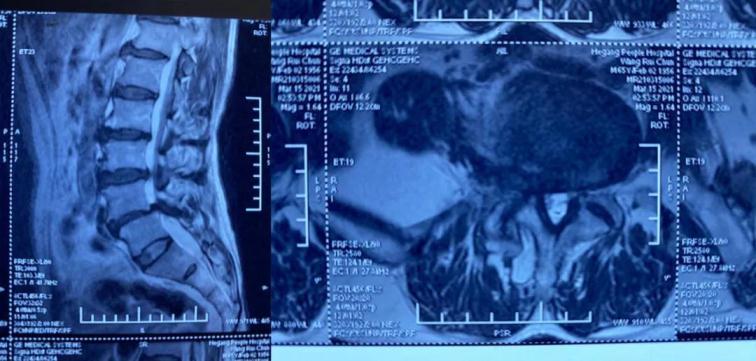

患者王某,男,65歲,腰痛伴右下肢麻痛1年,坐起及行走時(shí)疼痛明顯加重,行走不足100米即疼痛難忍需要休息,保守治療無效,嚴(yán)重影響生活質(zhì)量。慕名來到我院并找到喬院長(zhǎng)尋求治療?;颊呷朐汉?,經(jīng)過喬院長(zhǎng)認(rèn)真細(xì)致的檢查,診斷為:腰椎管狹窄、腰椎滑脫。

術(shù)前MRI